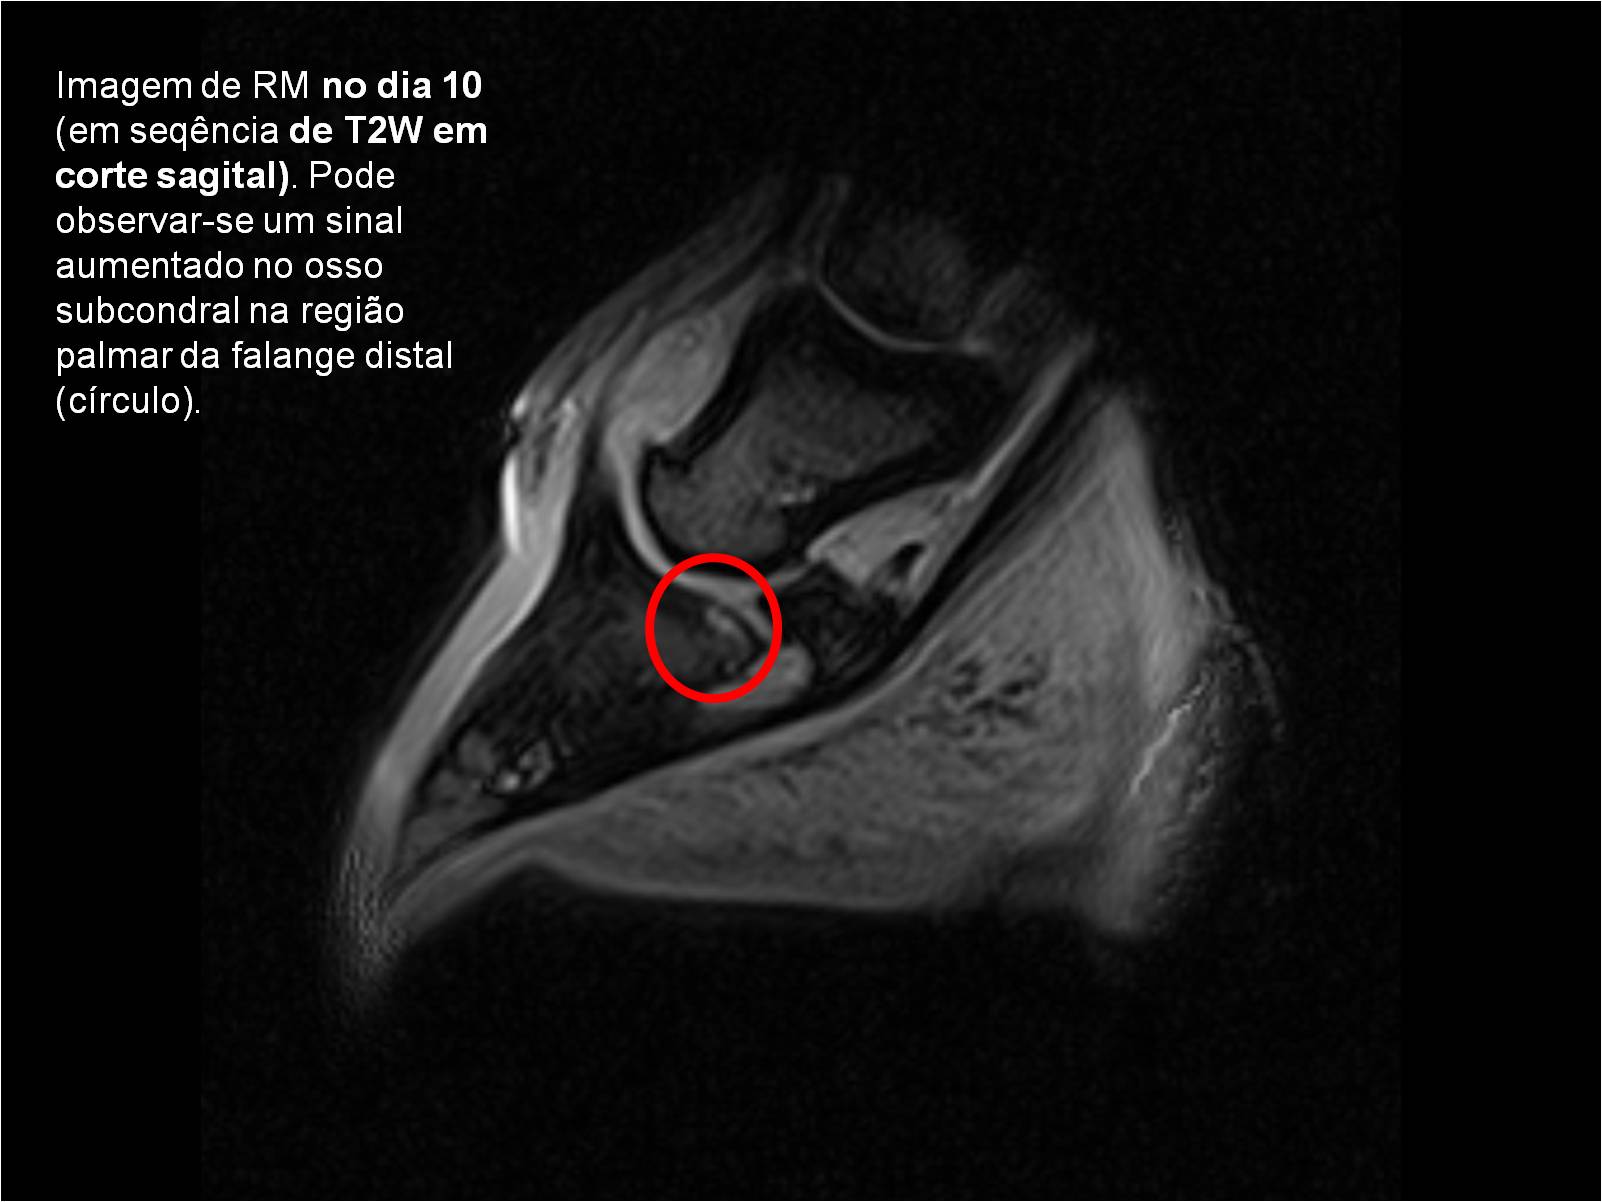

Publisher: Universidade de Évora

Abstract: O relatório de estágio encontra-se estruturado em três partes distintas. A primeira parte faz a caracterização das infraestruturas e funcionamento do Hospital Veterinário de Equinos de Lüsche, Oldenburg, Alemanha, assim como a análise casuística dos casos clínicos acompanhados durante os 6 meses de estágio. A segunda parte consiste de uma revisão bibliográfica sobre quistos do osso subcondral em equinos. Por fim, a terceira parte consta da apresentação e discussão de um caso clínico, nomeadamente o diagnóstico e acompanhamento imagiológico, por ressonância magnética, de um quisto subcondral na terceira falange num cavalo adulto; ### Abstract Equine Practice- Subcondral bone cyst of the third phalanx This internship report is divided in three parts. The first part characterizes the infrastructure and function of the Equine Hospital Lüsche, Oldenburg, Germany, as well as the casuistic of the clinical cases accompanied during the 6 month internship. The second part consists in a bibliographic review of cystic lesions of the subchondral bone in equines. The third part consists in a case report, the diagnostic and imagiological accompaniment, by use of magnetic resonance imaging, of a subchondral bone cyst in the distal phalanx of an adult equine.